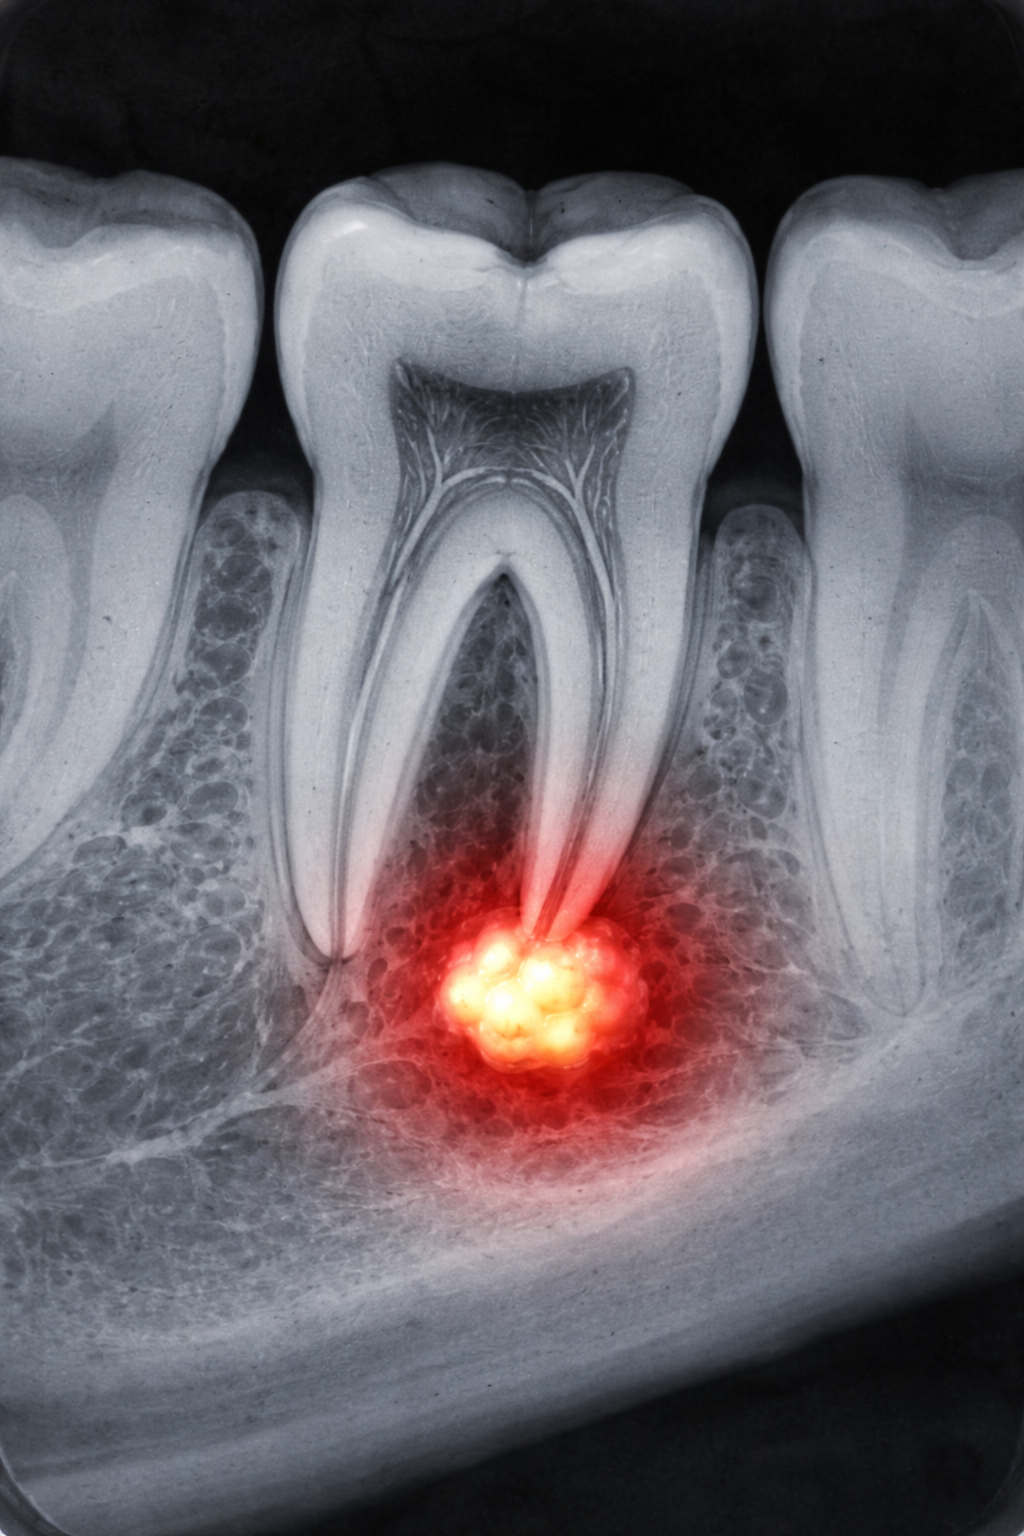

Peptide treatment for tooth decay

Imagine treating tooth decay with medication instead of a filling.